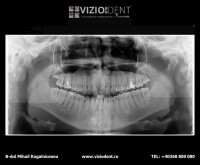

- radiografie panoramică

- radiografie panoramică 1/2

- radiografie panoramică bitewing